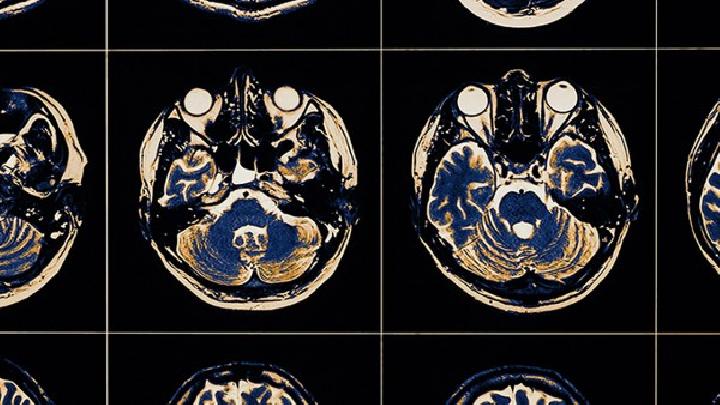

如果你想治疗和预防脑萎缩,知道脑萎缩的原因是非常重要的。它是一些脑部疾病中常见的疾病,因此了解其病因非常重要。那么,脑萎缩的原因是什么呢?让我们一起了解这个问题。以下是介绍。

2.脑损伤:持续癫痫发作和脑积水会导致脑萎缩。此外,老年人缺乏体力和脑力锻炼也可以加速大脑萎缩。这也是脑萎缩的原因。

3.遗传因素:经过对大量脑萎缩患者的调查和访问,近50%的患者有脑萎缩家族史。根据这些调查,有脑萎缩病史的家庭后代很有可能患上脑萎缩。这也是脑萎缩的原因之一。